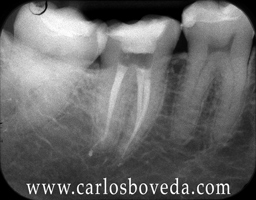

(para ver las rx a mayor tamaño haga click sobre ellas)